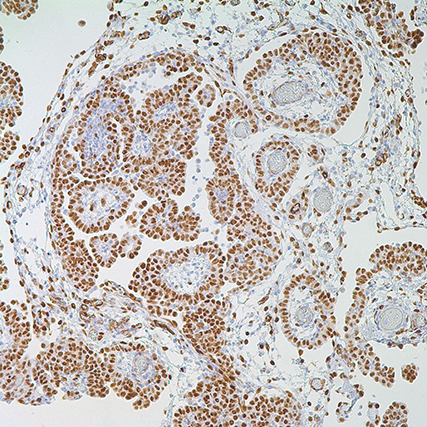

Wilms tumor 1 susceptibility wt1 gene products are selectively expressed in malignant mesothelioma am j pathol 1462. Wt1 is one of the most useful markers for identifying mesothelioma. Wt1 mutation in malignant mesothelioma and wt1 immunoreactivity in relation to p53 and growth factor receptor expression cell type transition and prognosis.

Doctors look for wt1 and other markers during mesothelioma diagnosis. As such the. Wt1 is a protein produced by the wilms tumor 1 gene.

Stains molecular markers wt1. Kicking off this summer the phase iii clinical trial is expected to build on the recent impressive success of a phase ii trial that helped the vaccine obtain the us. Wt1 protein is overexpressed found in higher than normal amounts on the surface of many types of cancer cells including most mesothelioma cells.

The best discriminators among the antibodies considered to be negative markers for mesothelioma are cea moc 31 ber ep4 bg 8 and b723. The wilms tumour susceptibility gene 1 wt1 expressed during transition of mesenchyme to epithelial tissues is regarded as a marker for the. This makes it a good immunohistochemical marker for mesothelioma.